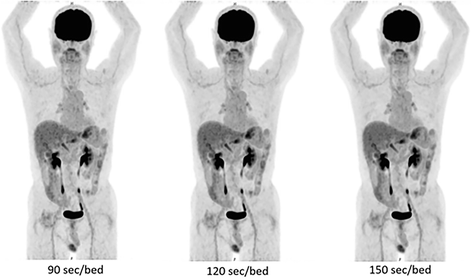

Figure 10 shows the images obtained from a male patient after treatment for intrahepatic bile duct cancer (age, 71 years; height, 159 cm; weight, 53.2 kg).

Sample clinical images with different acquisition times. This patient is a 71-year-old man with a height of 159 cm and a weight of 53.2 kg. Left: 90 s/bed position, middle: 120 s/bed position, right: 150 s/bed position. The PET scan was performed 63 min after the injection of 192.8 MBq (3.62 MBq/kg)

The PET scan was performed 63 min after the injection of 192.8 MBq (3.62 MBq/kg) of FDG. The blood sugar level just before the injection of FDG was 78 mg/dl. No visual difference was observed by two experienced imaging experts among the images reconstructed for 90, 120, and 150 s/bed position. Nonetheless, increased noise was observed in images acquired using 90 s/bed position (left panel in Fig. 9). The SUVmax and SUVmean in the liver, mediastinum, and brain are provided in Table 6. The differences in SUVmax and SUVmean among the three images were equal to or less than 0.12 in the liver, 0.08 in the mediastinum, and 0.56 in the brain.

Our QNR results indicate that 2 min/bed position are sufficient to meet the minimum recommendation of the Japanese guideline (QNR > 2.8). As shown in Fig. 9, the image obtained using 90 s/bed position looks a little noisy while those obtained using 120 or 150 s/bed position do not. The image obtained from 2 min/bed is thought to be of sufficient visual quality. In addition, the differences in SUVmax and SUVmean among the three images were small. The standard deviation of the SUVmean of the mediastinum and brain showed a decreasing tendency for longer acquisition time, but the differences were also small (Table 6). Considering the average height of the Japanese adult (approximately 170 cm for men, 160 cm for women), about nine bed positions are required for whole body scanning. Thus, an examination could be completed within 30 min including the entrance, positioning, and leave, which would be preferable for routine clinical use.